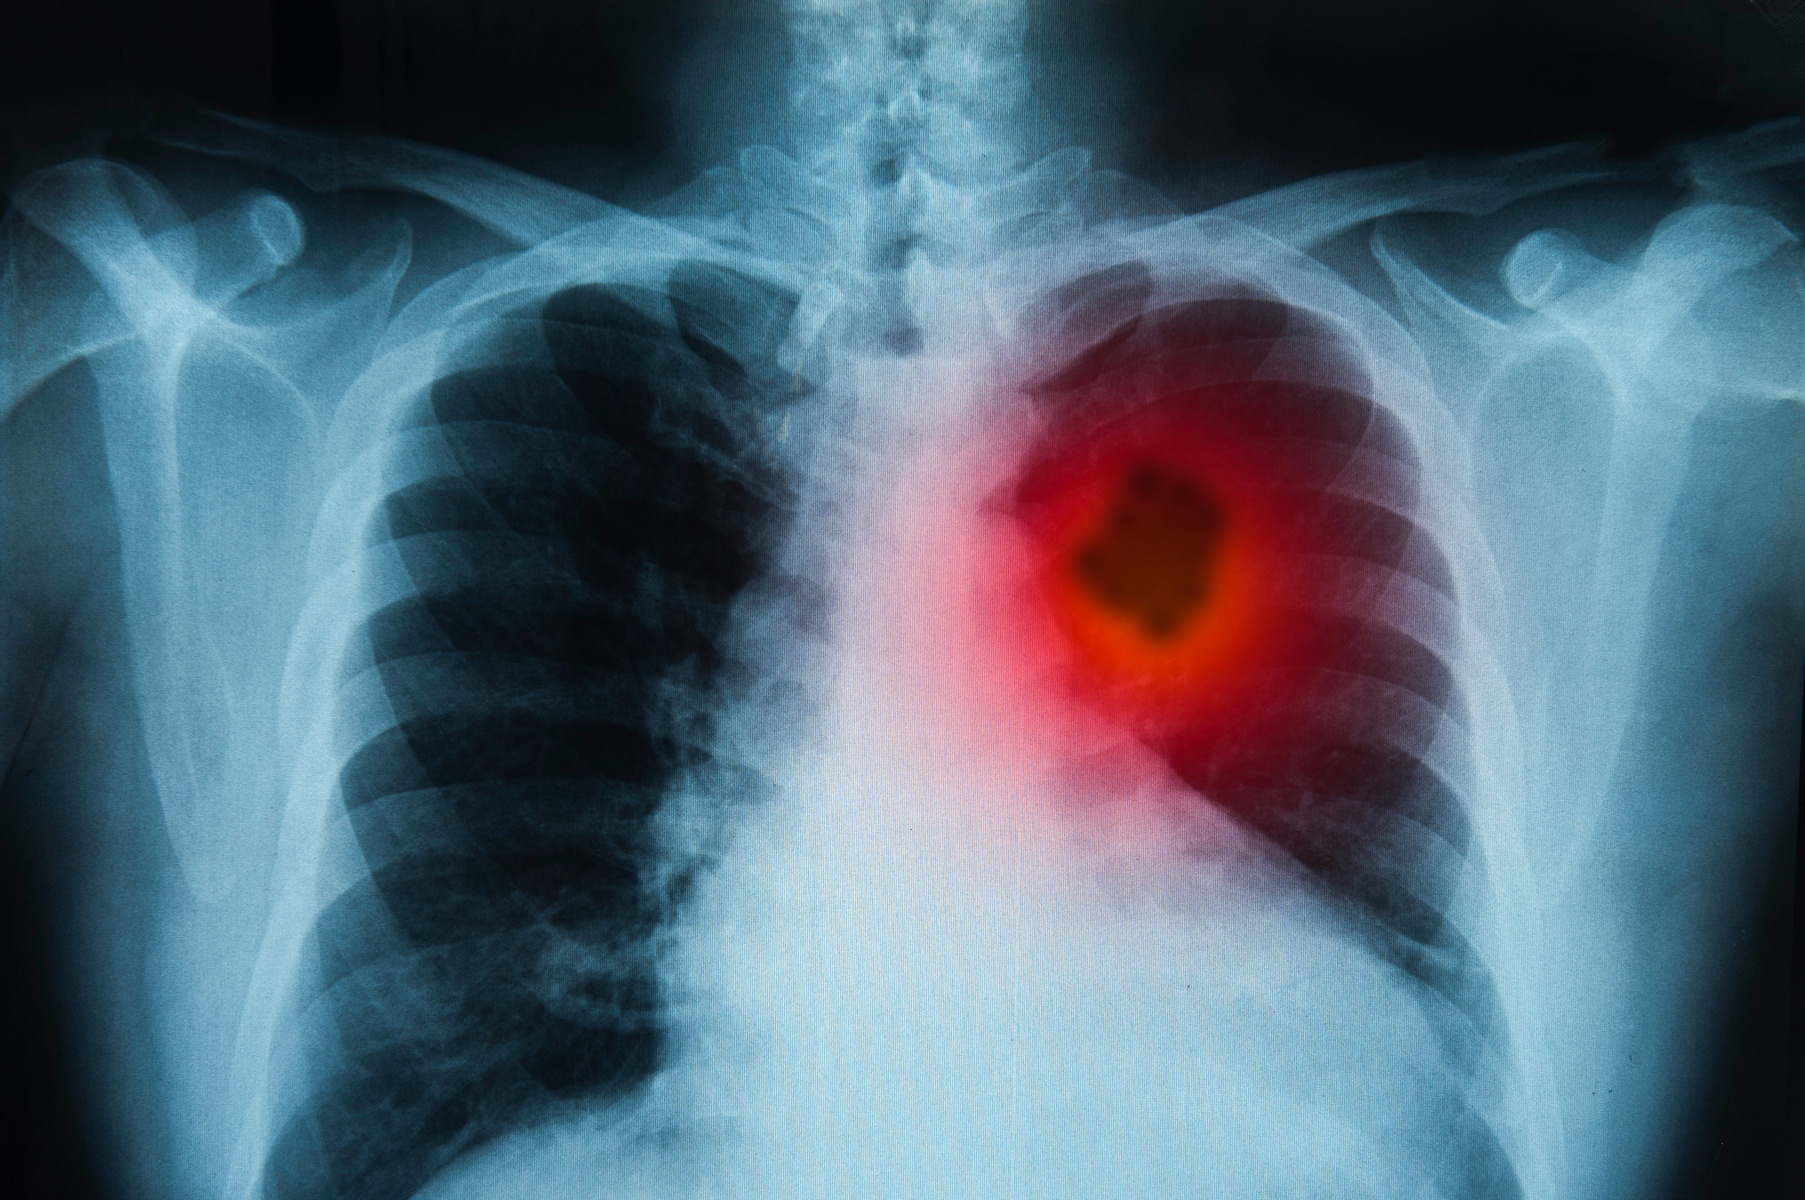

Tonoucí se stébla chytá: Léčba rakoviny experimentální vakcínou z garáže